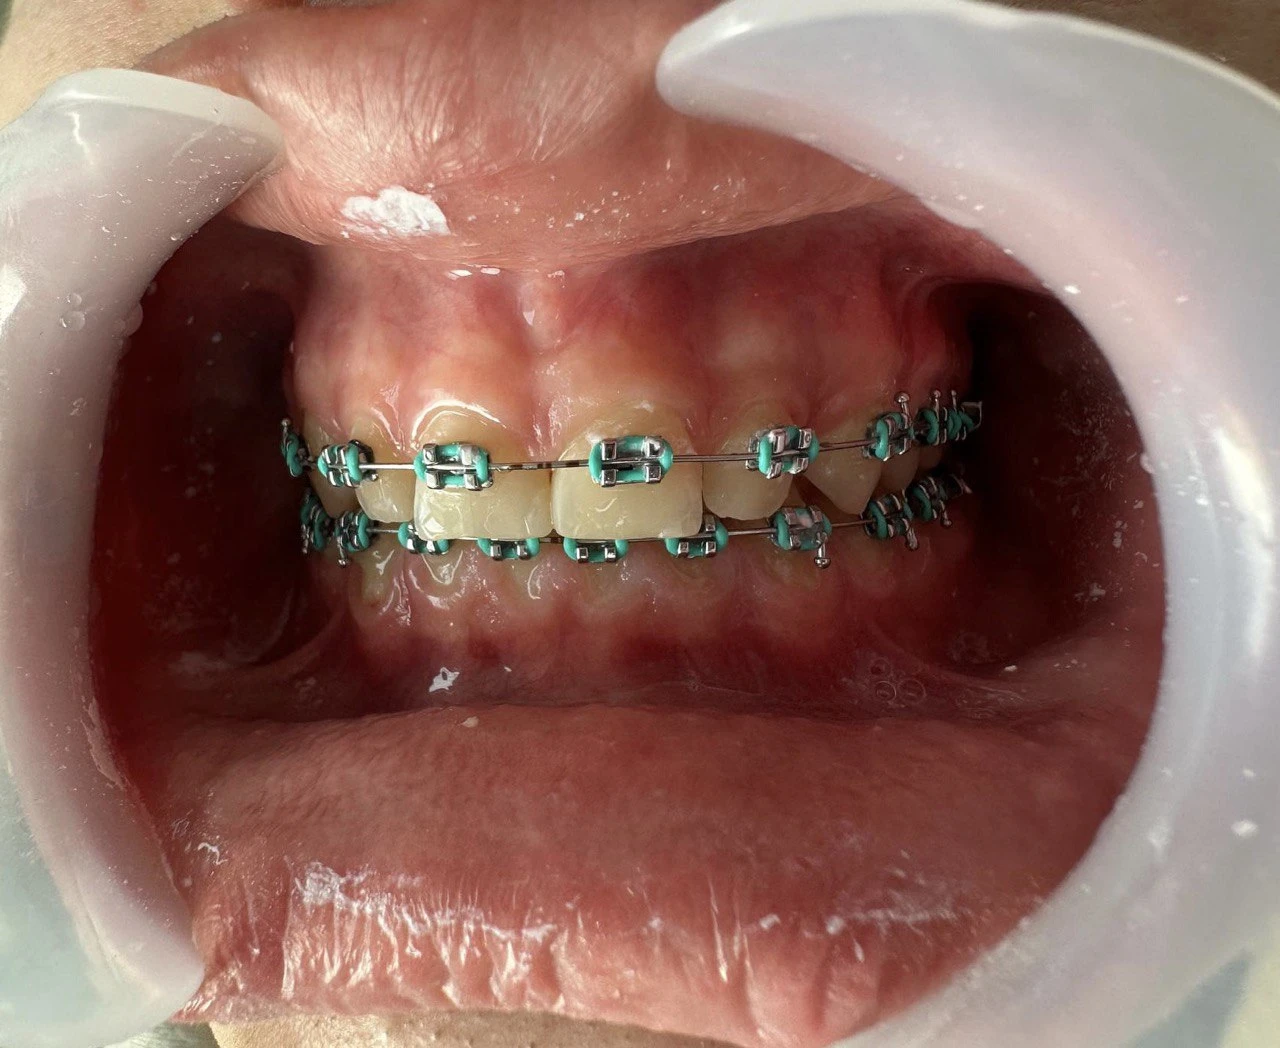

Ортодонтичне лікування дозволяє не лише вирівняти зуби, а й покращити функцію всього щелепного апарату. У MAXI Dent підбирають метод корекції індивідуально — від класичних брекетів до майже непомітних елайнерів. Процес лікування контролюється на кожному етапі, що забезпечує прогнозований результат. Наш підхід — максимально комфортно, естетично і без зайвих втручань.

Металеві та керамічні брекети

Самолігувальні системи

Наші результати роботи

Результати

*тисни, щоб побачити до/після